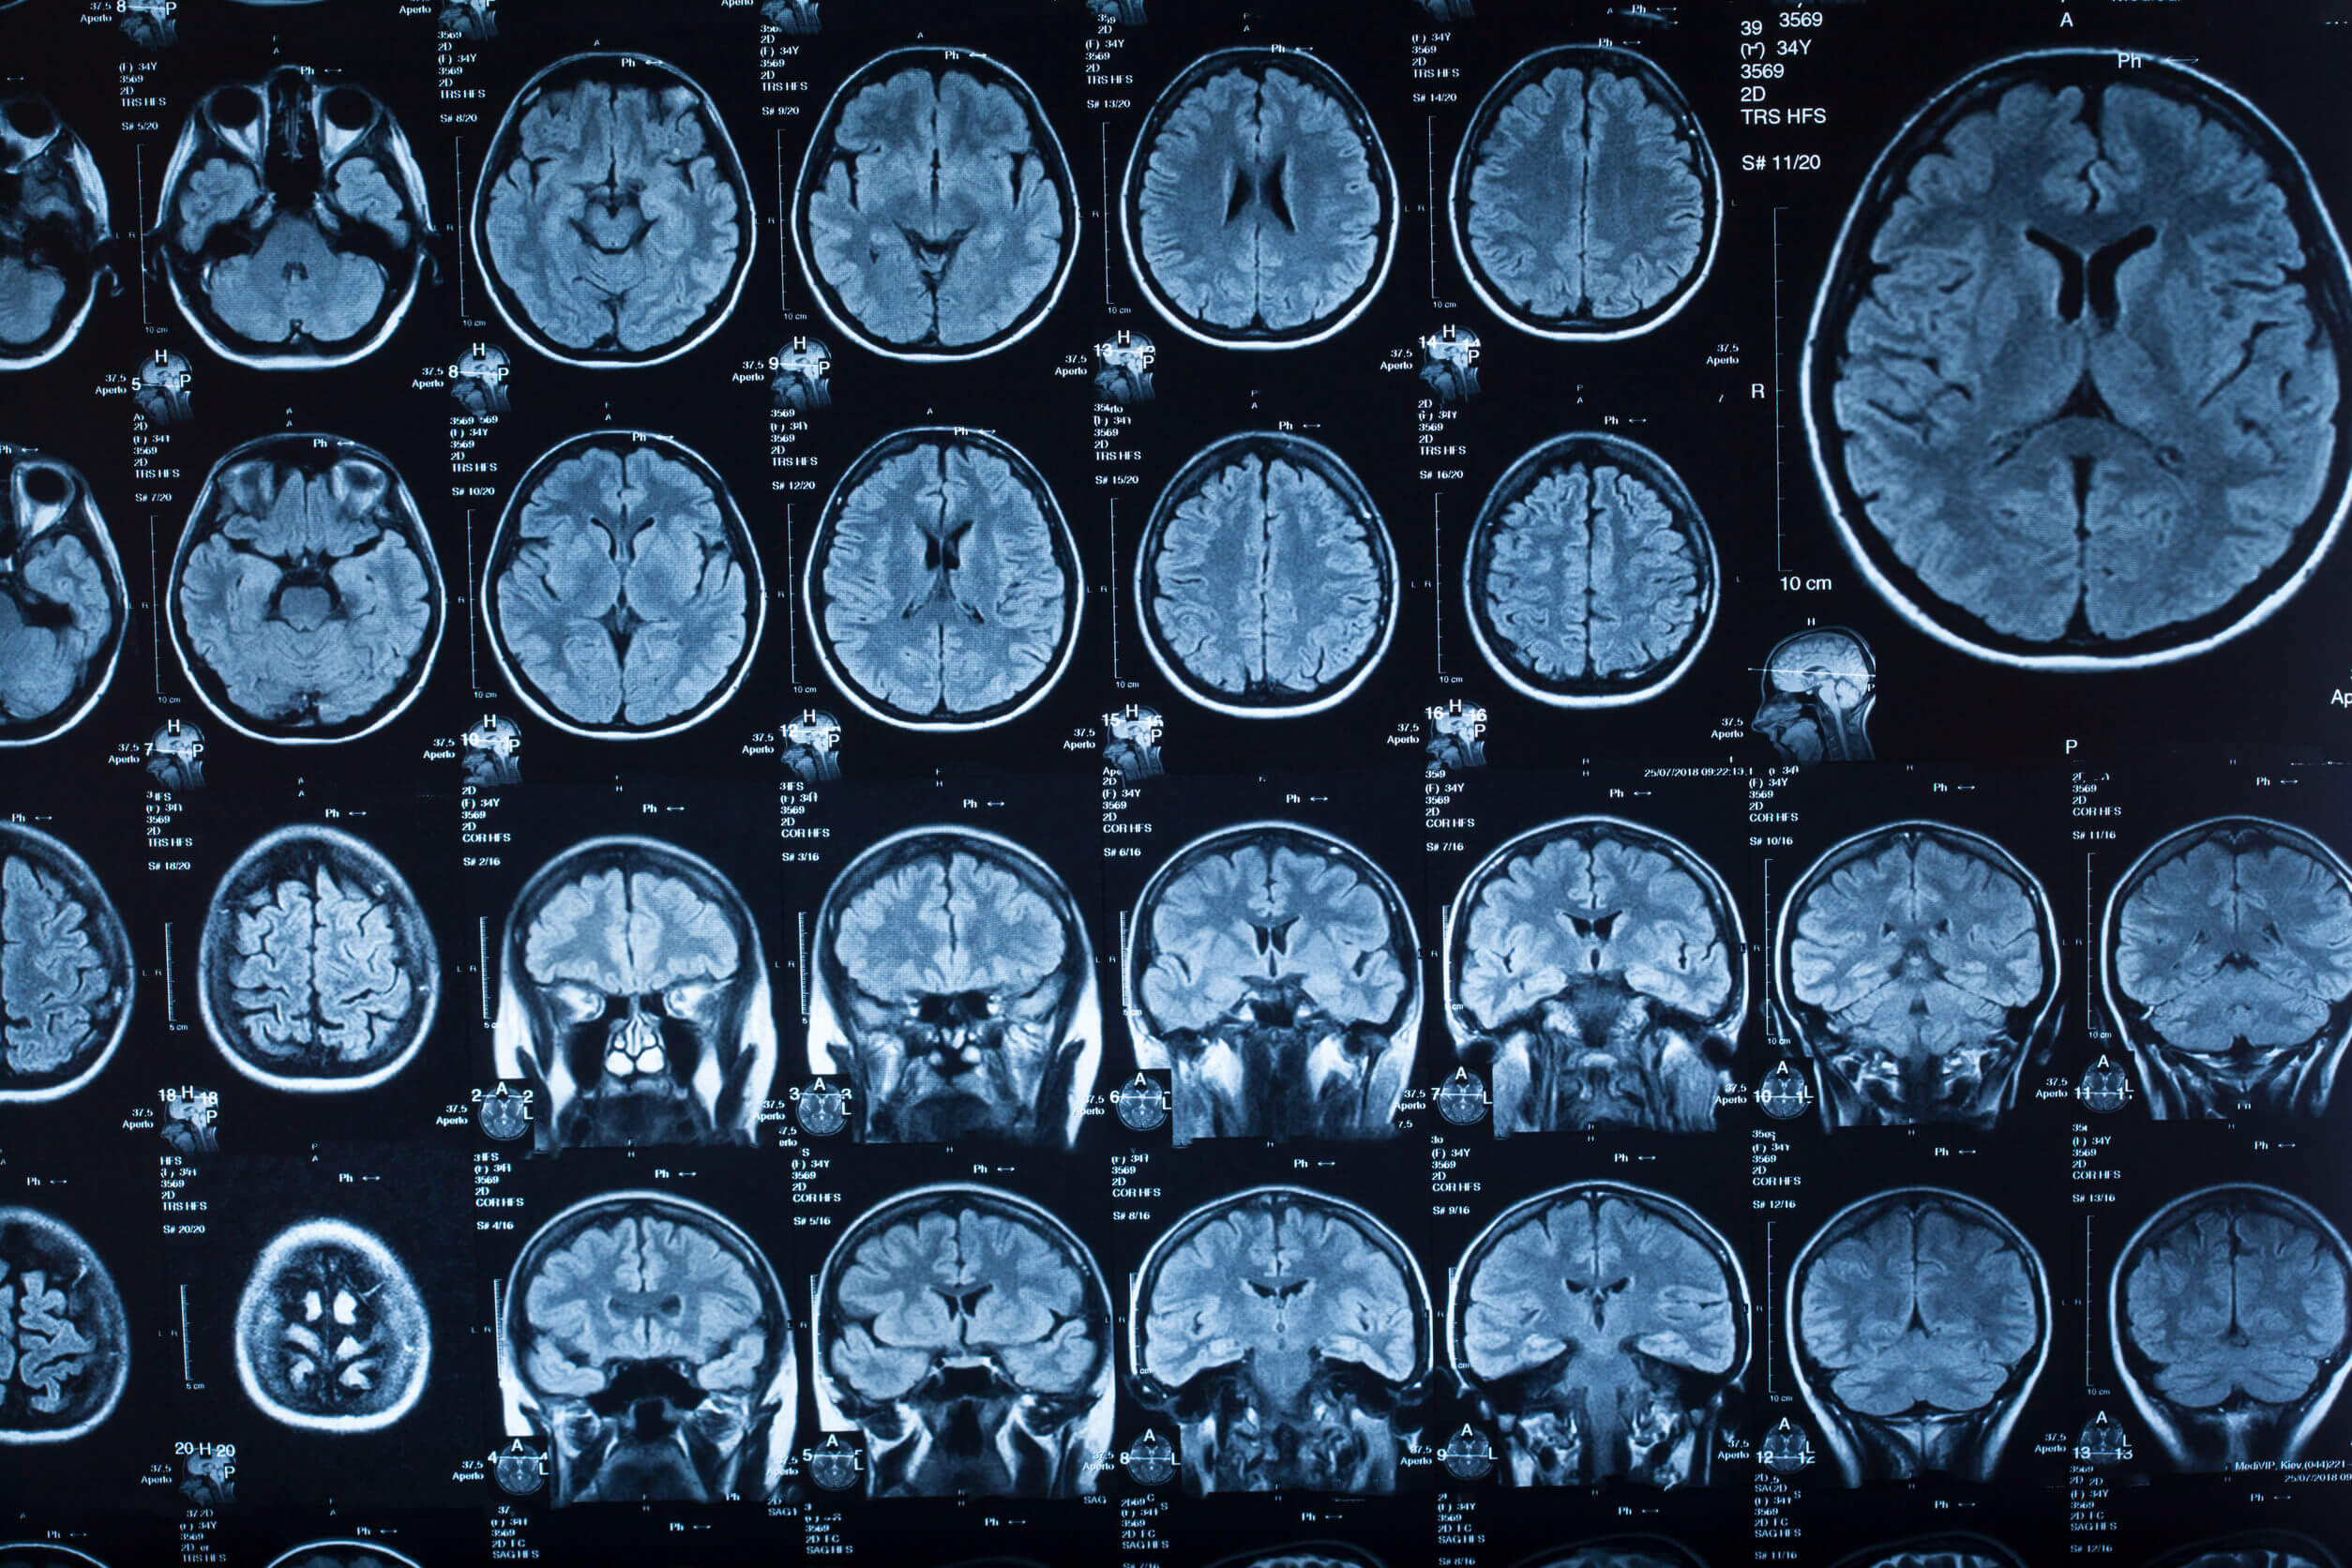

Dependiendo de la causa más probable, el médico podría indicar cualquiera de los siguientes estudios para complementar el diagnóstico clínico:

- Tomografía computarizada.

- Resonancia magnética nuclear.

Existen varias diferencias entre ambos estudios, en especial en lo referido al costo, calidad de imagen e indicaciones. Además, la tomografía computarizada emite radiación para trabajar, algo que no sucede con la resonancia.